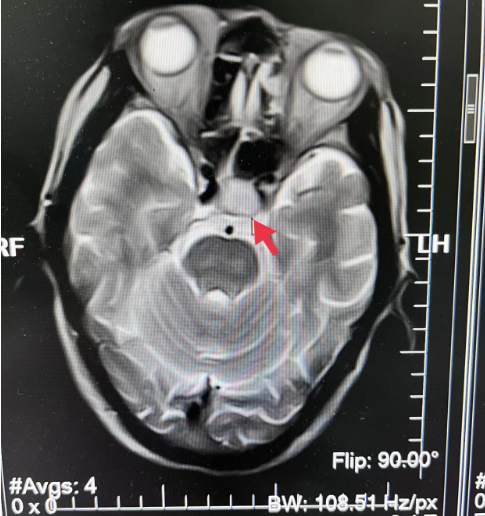

10、**男士,69岁

2023年9月8日在银川仁泰体检部体检,脑核磁检查提示:矢状位显示垂体窝内T2、T1WI示16.8*14.4mm等信号影,考虑脑垂体窝占位性病变,2023年9月12日通知客户到三甲医院进一步检查,明确病变性质,2023年9月20日跟踪回访,客户反馈已确诊为垂体瘤,正在住院做术前准备。